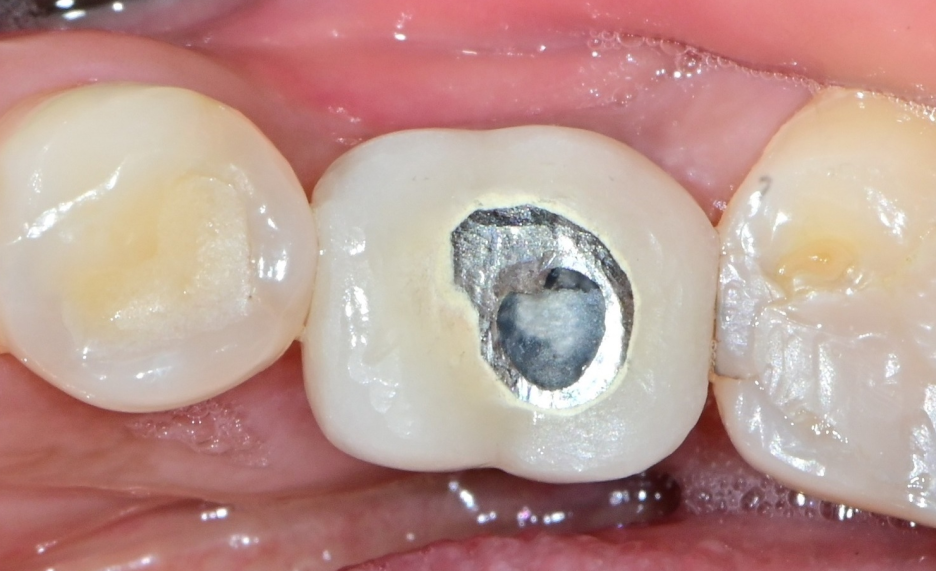

가장 흔한 원인은

✔ 교합 불균형

✔ 특정 치아에 힘 집중

| 파절로 내원 | 설계 | 제작완료 |

그래서 단순 교체가 아니라

👉 교합 분석 → 재설계 → 제작

과정을 통해

👉 재파절을 예방하는 것이 중요합니다.